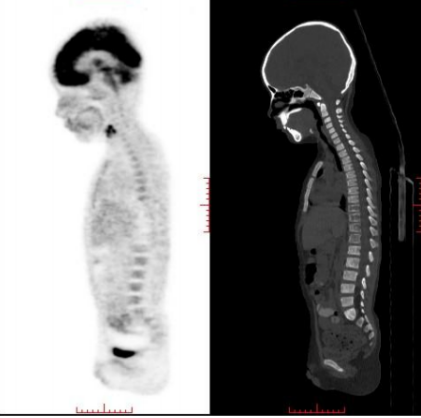

患儿,男,初诊年龄3岁5个月,2020年6月因“间断发热1月,左下肢疼痛1周”就诊,完善检查(PET/CT、骨髓MRD、骨髓活检病理)后诊断为M期高危神经母细胞瘤(NB)。

患儿初诊后接受规范化综合治疗:诱导治疗阶段完成8周期化疗(2020.06~2020.12)并行腹膜后肿物切除术;巩固治疗阶段因家庭经济原因未行自体造血干细胞移植,予瘤床放疗(Dt:23.4Gy/13f);维持治疗阶段口服维甲酸治疗(2021.03~2022.04)。PET/CT(2021.3.9)示左侧肾上腺术区未见异常高代谢灶,达到完全缓解(CR)。

PET-CT:左侧眼眶后壁骨质改变,伴灶周软组织肿块突向左侧眼眶后壁及左侧颞叶,考虑转移。

PET-CT(2023.09.15):左肾上腺区术后改变,术区未见肿瘤代谢活性病变,持续CR。

PET-CT(2024.11、2026.01):

未见代谢活性增高。